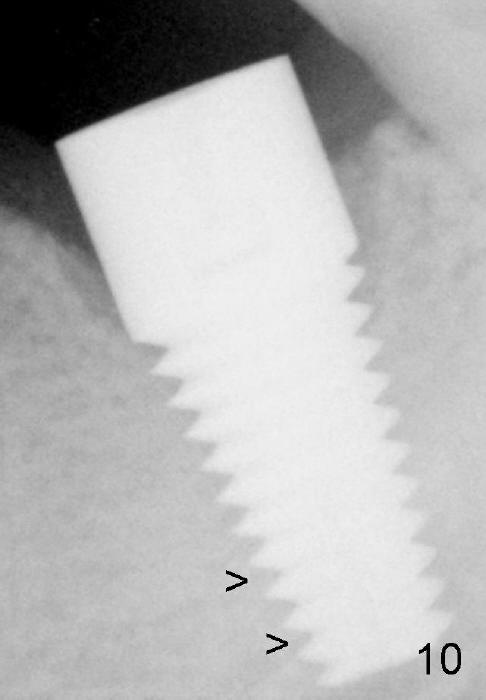

Osteo-integration occurs 7 months postop (Fig.10 >, as compared to Fig.6).